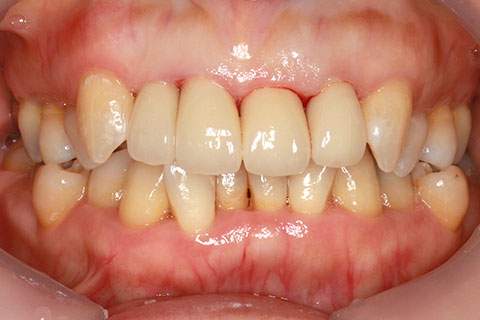

• オールセラミックの症例2

治療前

治療後

年齢・性別

45歳男性

治療期間

2ヶ月

抜歯

なし

治療費

70.4万円

備考

前歯8本の歯列不正によるセラミック治療

治療内容

歯質を削除し、セラミック冠をセメント合着

施術の副作用(リスク)

知覚過敏、歯髄炎、荷重負担